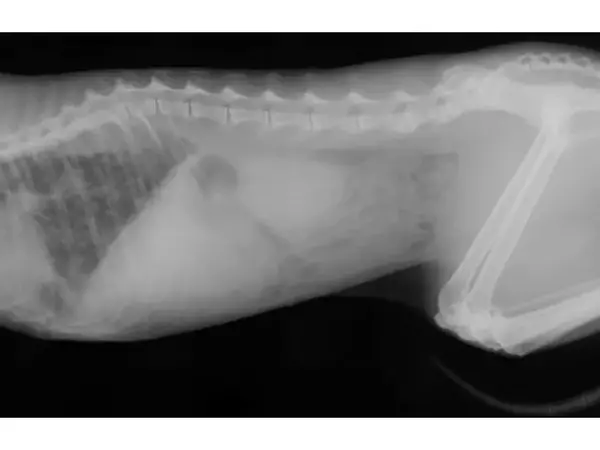

Навременното лечение на парализа при котка може да повиши чувствителността или дори да възстанови двигателната активност на крайниците.